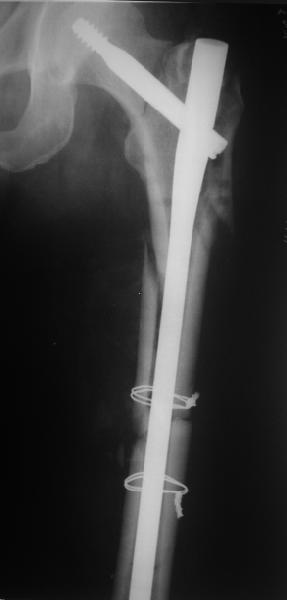

Изначально была выбрана не правильная точка введения стержня, в связи с чем в конце, я подчеркну, в конце операции произошло из-за напряжения между прокимальным концом канала бедра и стержнем разрушение в/3 бедра.

Проволока наложена потому, что при введении штифта не прошли эту зону римером и произошли сколы на концах отломков.

В общем, сделали. См. приложение.

Длина и из-за этого ось получились не совсем такие, как хотелось бы, все-таки срок после той операции уже 6 недель. Может быть, стоило провести дистракцию аппаратом неделю-другую. Заранее спасибо за комментарии и критику.